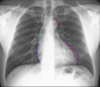

Quais e quantos são os arcos mediastinais no RX de Tórax?

5 arcos mediastinais

Dois a Direita

1. Veia Cava Superior

2. Átrio Direito

Três a Esquerda

3. Crossa da aorta

4. Tronco da artéria pulmonar

5. Ventrículo Esquerdo

O 4<u>o</u> arco mediastinal esquerdo aparece em que condição?

Aparece em aumento do átrio direito

Explique o sinal do duplo contorno

Ocorre com o aumento do átrio esquerdo que se projeta no campo pulmonar direito marcando assim sua silhueta